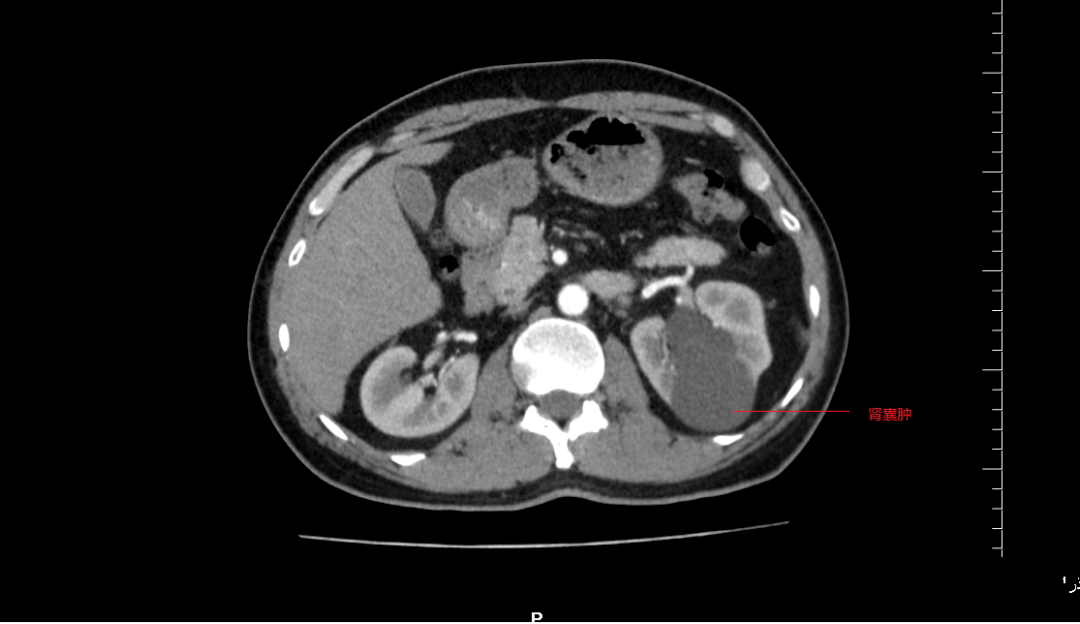

本以为是普通的腰疼,没想到检查发现左肾里竟同时藏着“结石”和“大囊肿”两个隐患。近日,一名47岁的男性患者在阳山县人民医院泌尿外科接受了左输尿管软镜下钬激光碎石取石术,同时通过经尿道输尿管软镜下肾囊肿内切开引流术,一次手术解决了两个棘手问题。术后患者恢复迅速,已顺利出院。 体检发现“双雷”埋伏 47岁的张先生(化名)最近因腰部不适来我院就诊。原本以为只是劳累所致,没想到B超和CT检查结果却让他大吃一惊:他的左肾不仅有多发结石,还长了一个巨大的肾囊肿。 这种情况在临床上并不少见,但同时处理起来却颇为棘手。泌尿外科医生介绍,传统的治疗方案往往需要“分步走”:要么先通过经皮肾镜(在腰上打孔)处理结石,后期再处理囊肿;要么通过腹腔镜手术“剥”掉囊肿,但对结石却难以兼顾。这意味着患者可能要经历两次手术、两次麻醉,不仅身体创伤大,恢复周期长,也增加患者经济负担。 巧妙设计:“借道”尿道,一箭双雕 考虑到患者年仅47岁,对生活质量要求高,且非常希望避免在身体上留下多处疤痕,我院泌尿外科团队经过详细的术前讨论,决定为其实施输尿管软镜下的一期手术。 这个手术的奥妙在于“借道而行”。医生利用人体天然的泌尿系统腔道——尿道,将纤细灵巧的输尿管软镜送入肾脏。 1. 先碎石: 抵达左肾后,医生首先发现了那些“捣乱”的结石。通过软镜的工作通道,插入钬激光光纤,将结石精准击碎成粉末状或小碎片,较大的碎片可直接用套石篮取出 。 2. 后开窗: 碎石完成后,镜头一转,找到了那个压迫肾实质的囊肿。在软镜的直视下,医生换用钬激光在囊肿壁最薄、最靠近肾集合系统的位置切开一个“小窗”,让囊液能够顺畅地流入肾盂,顺着尿液排出体外,从而达到内引流减压的目的 。 就这样,一根软镜,两种操作,患者腰上的两颗“雷”被一次性安全拆除。 微创领域的“黑科技” 输尿管软镜技术被誉为泌尿外科医生的“第三只眼”。其头端可以 270度弯曲,能轻松到达肾脏的各个角落,处理传统硬镜无法触及的结石和病变 。 而将其应用于肾囊肿内切开引流,更是近年来微创理念的延伸。相比于传统的腹腔镜或开放手术,这种术式拥有无可比拟的优势 : 真正无痕: 手术完全经自然腔道进行,体表没有任何切口,满足了现代患者对美观的需求。 同期治疗: 如张先生这般,可以一次麻醉处理多个合并疾病,避免了二次住院的麻烦。 恢复迅速: 由于手术创伤极小,患者术后疼痛轻。文献数据显示,此类手术患者术后住院天数通常仅为3天左右 。张先生术后恢复顺利,很快便康复出院。 术后康复与新生活的开始 术后,张先生的腰部胀痛感明显缓解。复查显示,左肾结石已清理干净,囊肿也已成功“瘪”了下去。他感慨地说:“原本以为要在身上打两个洞,甚至做两次手术,没想到睡一觉起来,两个问题都解决了,身上连个创可贴都没贴。” 此次手术的成功,标志着我院泌尿外科在处理肾脏复合性疾病方面迈上了新台阶。我们也将继续探索和运用更先进的微创技术,让更多的患者能享受到“损伤小、恢复快、效果佳”的优质医疗服务。 门诊地址:门诊楼2楼泌尿外科诊室 住院部地址:外科楼(5号楼)9楼 联系电话:0763-7816525 杨竞锋 主任医师 阳山县人民医院泌尿外科主任,主任医师。广州医科大学临床医学专业毕业,1993年7月参加工作。从事大外科临床工作10余年,泌尿外科专科工作10余年。曾多次在广州市三甲医院进修泌尿外科专业。擅长尿路结石及良性前列腺增生微创治疗,熟练开展前列腺整体剜除术等四级手术,临床经验丰富。现任清远市医学会泌尿外科分会常务委员,清远市医学会男科分会委员,广东省泌尿生殖尿控分会委员。曾主持市级课题2项,以第一作者或通讯作者发表论文近10篇。 封长其 副主任医师 阳山县人民医院泌尿外科副主任,副主任医师,医学学士,2008年毕业于贵州医科大学临床医学系。从事泌尿外科临床、教学工作10余年,2018年到广东省第二人民医院泌尿外科进修,以第一作者发表省级医学论文多篇,擅长泌尿系结石、前列腺增生的微创手术,擅长泌尿外科常见开放手术治疗,熟悉泌尿外科腹腔镜手术,对泌尿外科急危重患者管理积累了丰富的经验。对泌尿外科肿瘤(如肾癌、膀胱癌、前列腺癌、肾上腺肿瘤)以及泌尿系畸形的治疗及手术亦积累了较多经验。 陈宇航 副主任医师 阳山县人民医院泌尿外科副主任医师,科室技术骨干,广州医学院临床医学本科,2001年7月参加工作,擅长泌尿外科常见病、多发病诊治及微创手术。